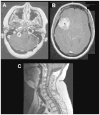

Neurofibromatosis type 1 (NF1) is one of the most common brain tumor predisposition syndromes, in which affected children are prone to the development of low-grade gliomas. While NF1-associated gliomas can be found in several brain regions, the majority arise in the optic nerves, chiasm, tracts, and radiations (optic pathway gliomas; OPGs). Owing to their location, 35-50% of affected children present with reduced visual acuity. Unfortunately, despite tumor stabilization following chemotherapy, vision does not improve in most children. For this reasons, more effective therapies are being sought that reflect a deeper understanding of the NF1 gene and the use of authenticated Nf1 genetically-engineered mouse strains. The implementation of these models for drug discovery and validation has galvanized molecularly-targeted clinical trials in children with NF1-OPG. Future research focused on defining the cellular and molecular factors that underlie optic glioma development and progression also has the potential to provide personalized risk assessment strategies for this pediatric population.